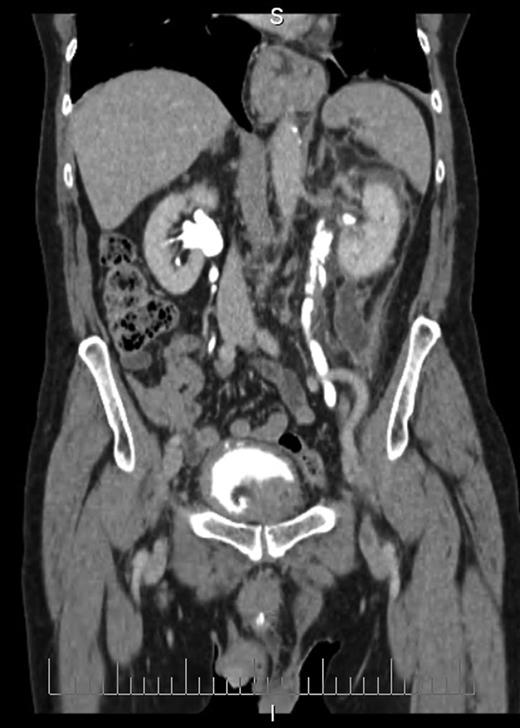

Blood tests revealed a Stage 3 acute kidney injury (baseline renal function was normal) with raised inflammatory markers and elevated PSA compared with baseline (Table 1). A mid-stream urine specimen sent for microscopy, cultures and sensitivities yielded no growth of organisms. A bedside bladder scan revealed a bladder volume of >999 ml, necessitating the insertion of a urethral catheter with a residual volume of 2.4 l, and intravenous antibiotics were commenced. An ultrasound scan (USS) of the urinary tract was performed to evaluate for the presence of hydronephrosis; but while this demonstrated a minor dilatation of the left renal pelvis, it also found a shallow fluid collection around the left kidney extending into the left lateral retroperitoneum, separate from the left psoas muscle (Fig. 1). In the urinary bladder, there was an irregular 4 cm mass on the left posterolateral aspect. In view of the findings, an urgent flexible cystoscopy was performed, revealing a massive median lobe of the prostate protruding up and back into the bladder; the ureteric orifices were not visualized because of this, and the bladder mucosa was normal. The patient subsequently underwent a computed tomography (CT) urogram, which showed bilateral fullness in the pelvicalyceal systems and confirmed a 4.8 × 4.4 × 2.8 cm fluid collection adjacent to the lower pole of the left kidney as detected on the USS, with perinephric stranding. The fluid collection was demonstrated to be extravasated urine on the delayed post-contrast images arising from a defect in the left proximal ureter, and extending down the left paracolic gutter (Figs 2 and 3). The massive prostate was also demonstrable (Fig. 3).

Coronal section CT image demonstrating fluid collection extending down left paracolic gutter. Also visible are massively enlarged prostate and urinary extravasation from left ureter.

Severe intractable abdominal pain similar to that attributed to renal colic is the most observed presentation of ureteral rupture [1, 6], and its presence is confirmed on imaging, which may be performed to investigate other causes of pain. CT scan of the urinary tract with a delayed excretory phase of contrast is likely to be the most used means and can determine the presence of extravasation, likely location of rupture and extent of urinoma or abscess formation, as well as the nature of the obstructing lesion. If retrograde ureteral stent placement is to be performed, then pyelography can be performed at the same time to confirm CT findings. Ultrasonography has a limited role for detecting ureteral pathologies but was key here in detecting a perinephric fluid collection and possible bladder mass, which led to further investigations.